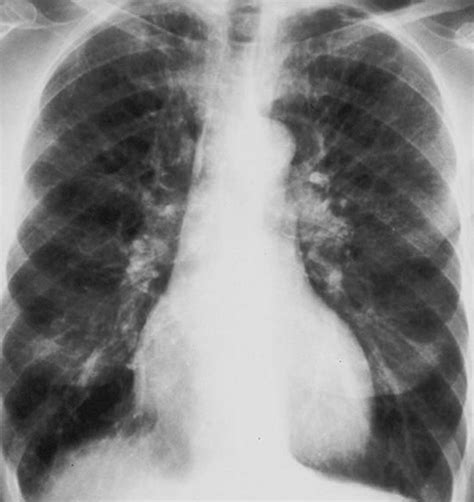

- Enfermedades pulmonares: EPOC (bronquitis crónica, enfisema), asma, embolia pulmonar.